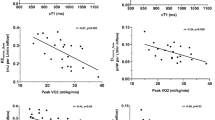

We sought to evaluate the potential clinical role of 4D-flow cardiac magnetic resonance (CMR)-derived energetics and flow parameters in a cohort of patients’ post-Fontan palliation. In patients with Fontan circulation who underwent 4D-Flow CMR, streamlines distribution was evaluated, as well a 4D-flow CMR-derived energetics parameters as kinetic energy (KE) and energy loss (EL) normalized by volume. EL/KE index as a marker of flow efficiency was also calculated. Cardiopulmonary exercise test (CPET) was also performed in a subgroup of patients. The population study included 55 patients (mean age 22 ± 11 years). The analysis of the streamlines revealed a preferential distribution of the right superior vena cava flow for the right pulmonary artery (62.5 ± 35.4%) and a mild preferential flow for the left pulmonary artery (52.3 ± 40.6%) of the inferior vena cave-pulmonary arteries (IVC-PA) conduit. Patients with heart failure (HF) presented lower IVC/PA-conduit flow (0.75 ± 0.5 vs 1.3 ± 0.5 l/min/m2, p = 0.004) and a higher mean flow-jet angle of the IVC-PA conduit (39.2 ± 22.8 vs 15.2 ± 8.9, p < 0.001) than the remaining patients. EL/KE index correlates inversely with VO2/kg/min: R: − 0.45, p = 0.01 peak, minute ventilation (VE) R: − 0.466, p < 0.01, maximal voluntary ventilation: R:0.44, p = 0.001 and positively with the physiological dead space to the tidal volume ratio (VD/VT) peak: R: 0.58, p < 0.01. From our data, lower blood flow in IVC/PA conduit and eccentric flow was associated with HF whereas higher EL/KE index was associated with reduced functional capacity and impaired lung function. Larger studies are needed to confirm our results and to further improve the prognostic role of the 4D-Flow CMR in this challenging population.

Moreover, EL/KE index was associated with impaired functional aerobic capacity and reduced ventilation response at physical exercise. As a matter of fact, EL/KE index correlates significantly, inversely with VO2/kg/min: r: − 0.453 p = 0.010, peak VE r: − 0.453 p < 0.010, MVV − 0.437 p = 0.018 and positively with VD/VT peak: r: 0.581 p < 0.01 (Fig. 3).